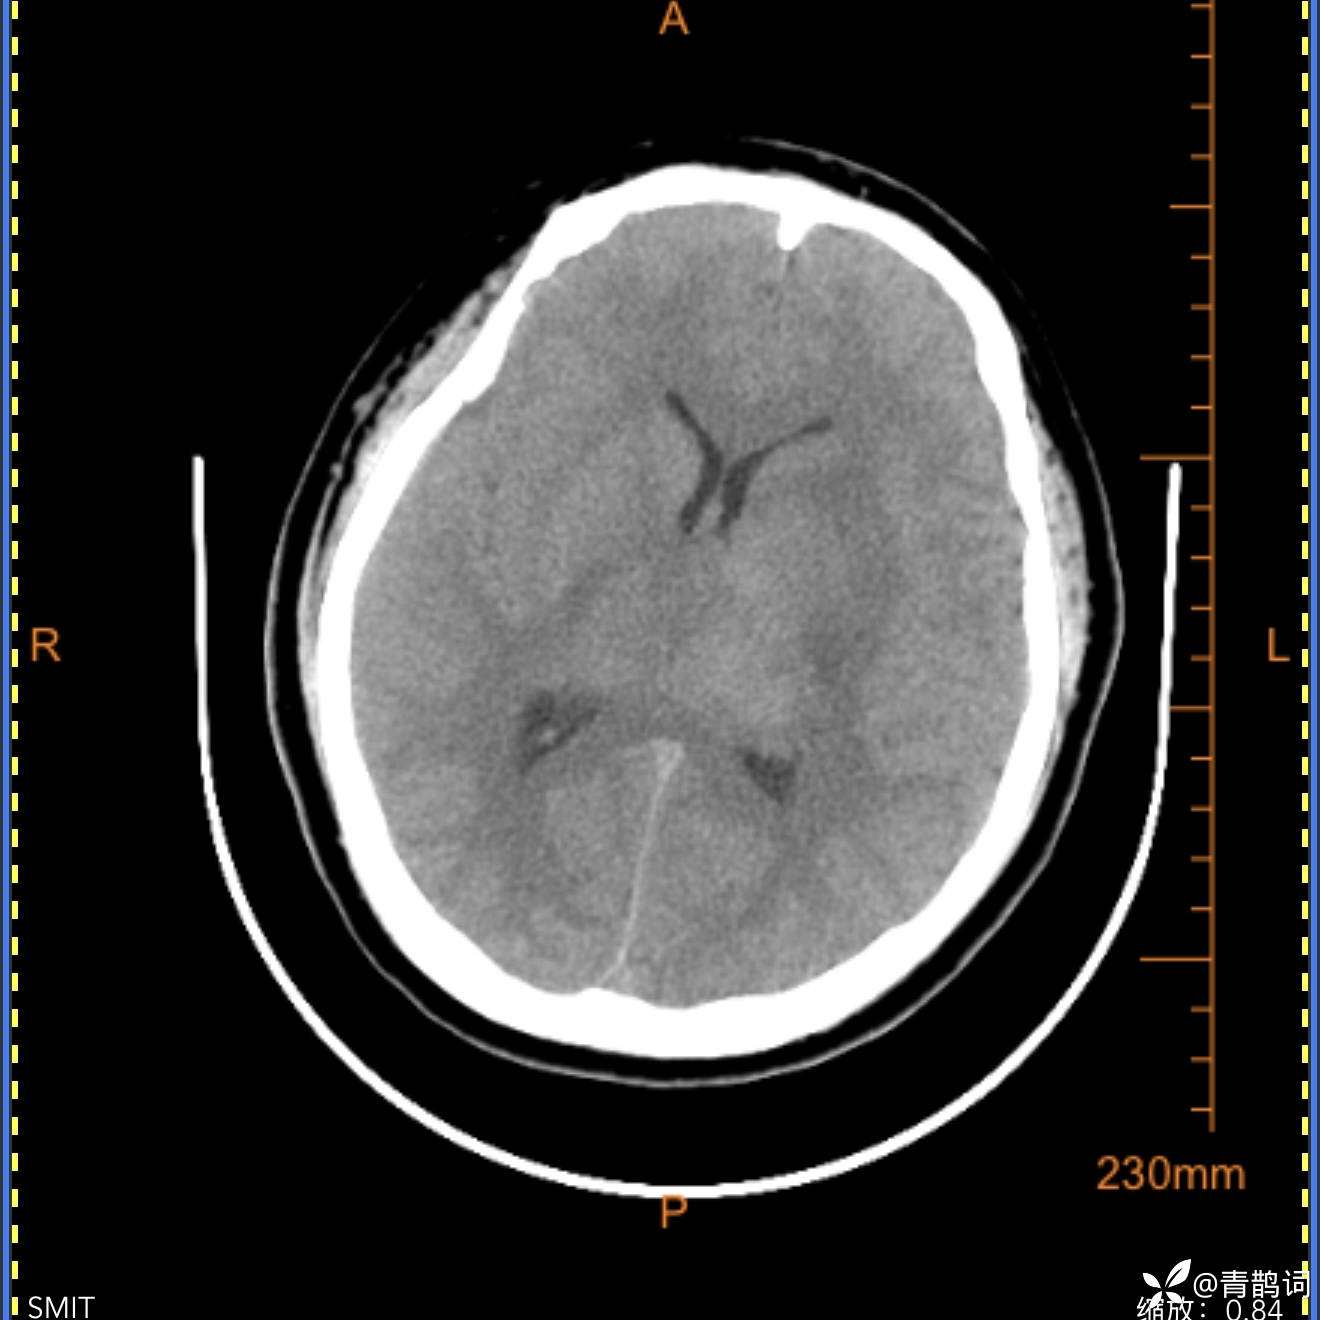

18岁男患,近期反复发热,体温最高达41摄氏度,自行口服退烧药物,效果欠佳,伴有头痛。无肢体无力,言语困难等症状。完善头部CT如下: